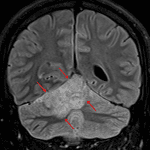

MRI

- Ill-defined T2/FLAIR hyperintense mass in the superior aspect of the right cerebellar hemisphere and superior aspect of the vermis measuring approximately 4.3 x 2.2 x 4.2 cm

- Nodular internal areas of restricted diffusion and corresponding patchy enhancement

- Peripheral susceptibility artifact about one of these nodular areas in the anterior aspect of the right cerebellar hemisphere, likely relating to hemorrhage

- Thickening and enhancement of the adjacent tentorial leaflet

- FLAIR signal hyperintensity in a right occipital sulcus and possible adjacent cortical FLAIR signal hyperintensity without definite corresponding restricted diffusion or enhancement (possibly representing leptomeningeal spread)

- Small focus of restricted diffusion along the interhemispheric fissure without definite corresponding enhancement (also possibly a leptomeningeal tumor deposit)

- Associated mass effect in the posterior fossa resulting in cerebellar tonsillar herniation and crowding of the fourth ventricle with mild obstructive hydrocephalus